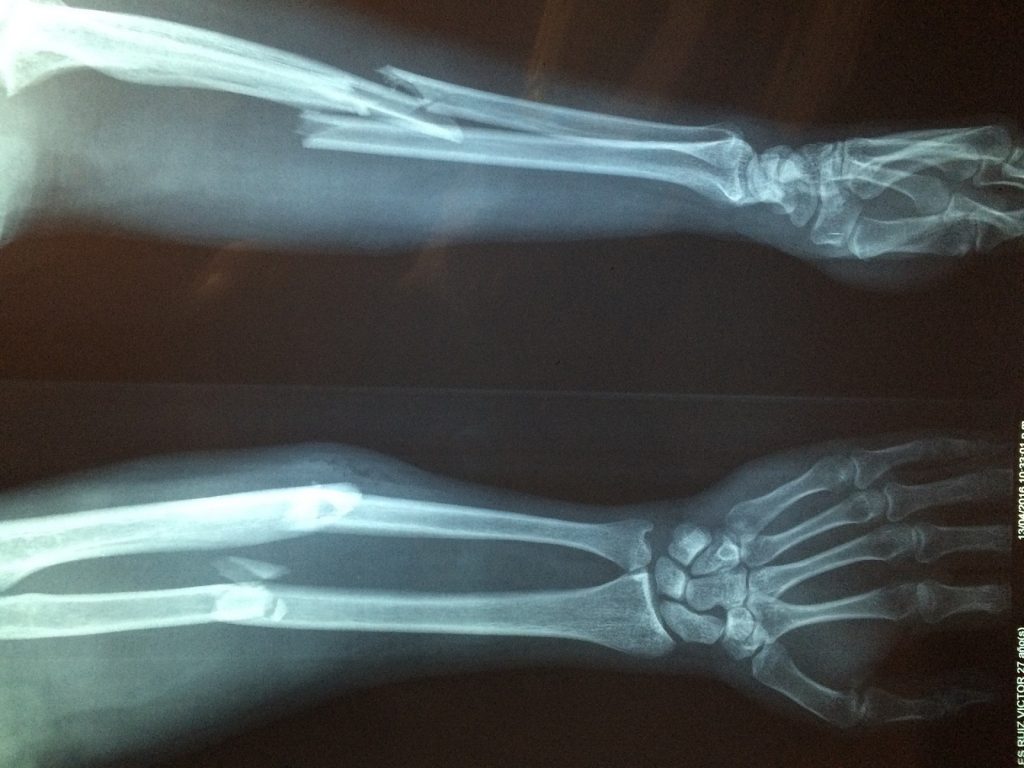

Bicyclists can sustain severe and sometimes fatal injuries in an accident, but the most common injuries are broken and fractured bones. Since bicyclists do not share the same protection as motorists, they are particularly susceptible to these types of injuries, especially if they are thrown from the bicycle. A bicyclist can sustain a broken bone even if he or she wears the proper protective gear.

Since bicyclists do not have the luxury of riding in an enclosed vehicle, they are especially susceptible to certain types of injuries. When a motorist and a bicyclist collide, the bicyclist is most likely to break bones in the following body parts.

- Wrist and hand